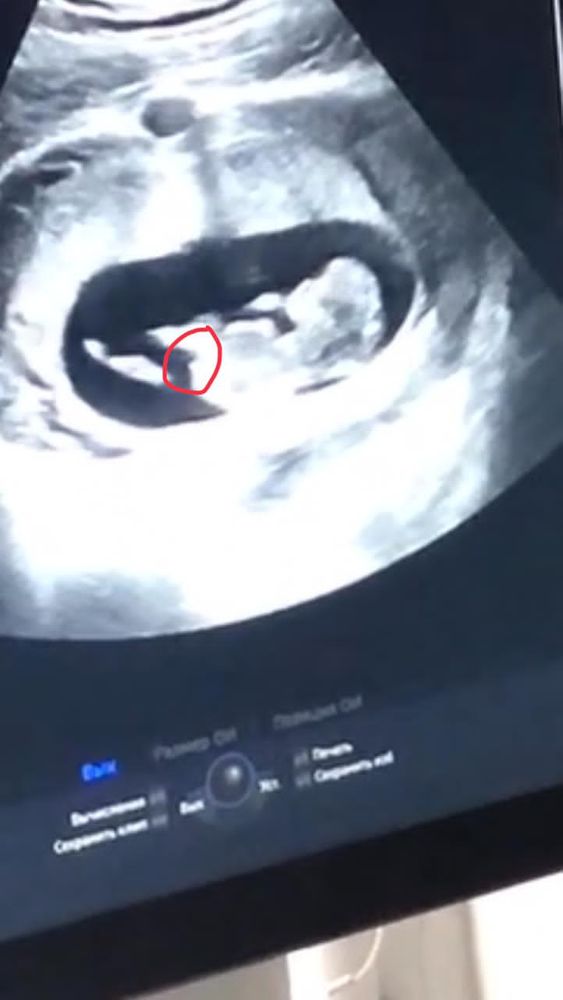

Сначала написала что девонька не туда посмотрела на фотке 😂😂 короче согласна с комментатором что мальчик. Свою на таком же сроке сама дома правильно определила. У вас уже прям так торчит этот бугорок вверх, у моей в таком размере когда была не торчал

Кристина, у меня было видео на котором я поймала стоп кадр. Я была уверена что у меня мальчик и все кругом говорили, но после этого стоп кадра поняла что девочка. Так и вышло, вопреки всем. Конечно плохо видно но можно заметить как торчит вдоль, а у вас прям на фотке очень вверх

Кто умеет: попробуйте определить пол малышей? ❤️18 недель, была на узи, сказали пол ребёнка